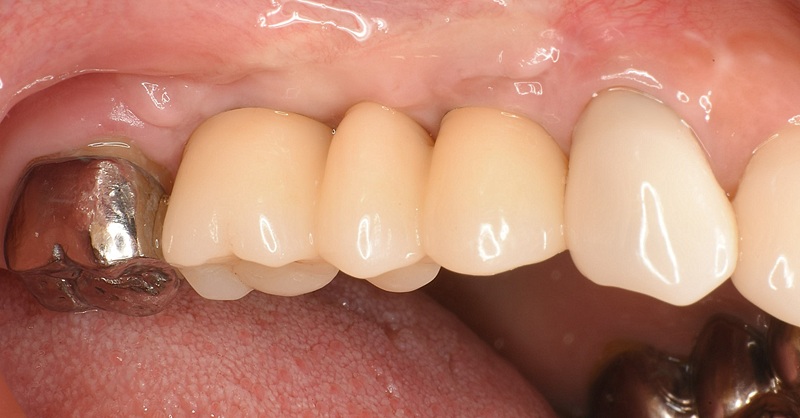

| 治療名 | GBRとインプラントを行った症例 |

| 治療説明 | インプラントを埋入予定の部位において、骨の吸収が見られたため、インプラント埋入と同時に小規模な骨造成(GBR)を行いました。治癒期間を経て、最終的にセラミックの上部構造を装着し、自然な見た目としっかりとした噛み合わせを回復しました。 |

| 治療回数・期間 | 6ヶ月 |

| 副作用とリスク | インプラント治療は、入れ歯やブリッジに比べて治療期間が長くなる傾向があります。骨造成が必要な場合は、さらに治療期間が延びることがあります。 また、手術後には一時的な違和感や痛み、腫れ、出血などが生じる場合がありますが、通常は2日〜1週間ほどで落ち着きます。 |

| 料金(税込) | GBR〈小規模骨造成〉:110,000円 インプラント一次手術:220,000円 二次手術:55,000円 上部構造〈セラミック〉:165,000円 合計:550,000円 |